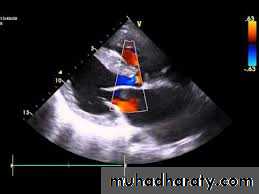

Echocardiography.

Two-dimensional and Doppler echo studies can identify the number, size, and exact location of the defect; estimate PA pressure; identify other associated defects; and estimate the magnitude of the shunt.